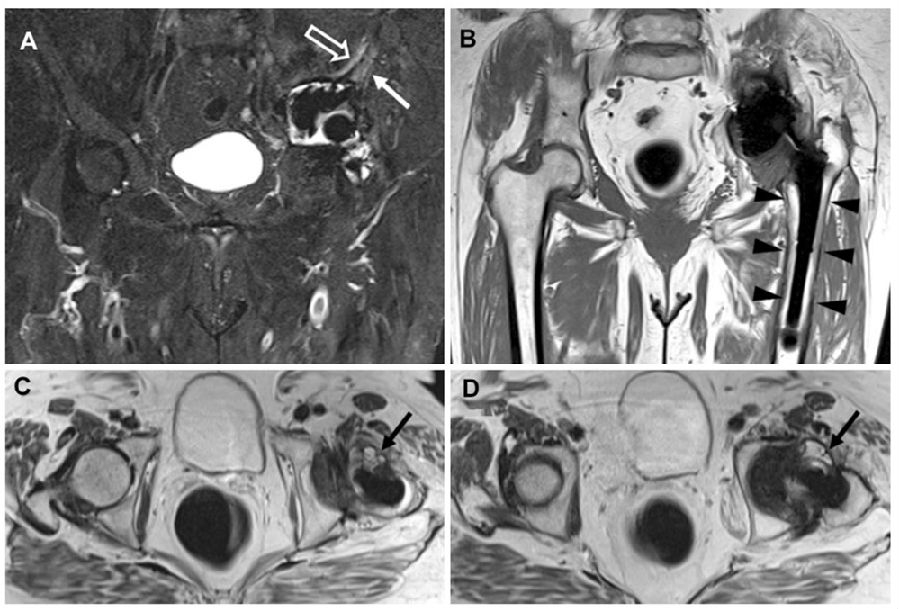

图9 一名77岁THA感染女性的骨盆MRI

冠状STIR(A)显示假体周围髋臼骨水肿(白色箭头)和囊外水肿(空心箭头)。冠状T1加权图像(B)中未发现骨破坏。轴位T2加权图像(C和D)显示炎症和滑膜炎